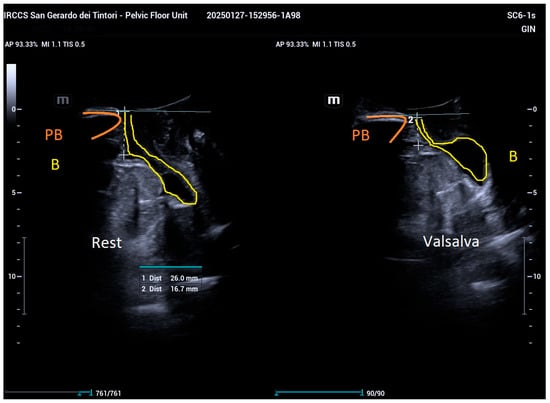

2.2. Ultrasound Examination